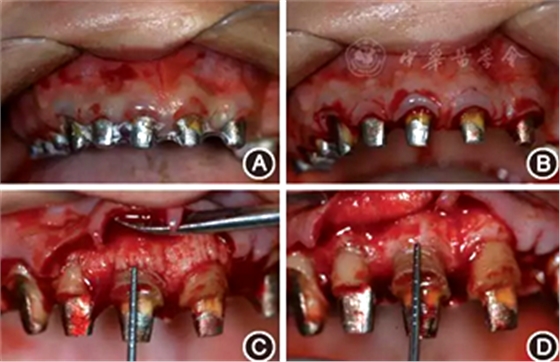

圖4 術前制作診斷蠟型及手術導板 A:診斷蠟型,確定最終修復體的形態(tài)及齦緣位置;B:透明墊式手術導板,用以指導手術切口的精確控制

(2)手術導板指導下的牙冠延長術:根據(jù)最終診斷蠟型,制作透明墊式手術導板(圖4B),指導上頜牙冠延長術(圖5),最終達到改善牙齦形、線、點的美學要求,獲得協(xié)調(diào)、對稱的美學效果。

圖5 有利于健康、功能及美學效果的牙冠延長術手術過程 A:戴入手術導板;B:在手術導板的指導下確定手術切口;C:翻瓣后可見唇側骨板肥厚、形態(tài)不佳,上前牙鄰面及唇側原有肩臺距離骨嵴頂≤ 2 mm,侵犯了生物學寬度;D:骨切除及骨成形后唇側骨板形態(tài),肩臺距牙槽嵴頂約4 mm;E:齦瓣復位縫合,原有肩臺均位于齦上